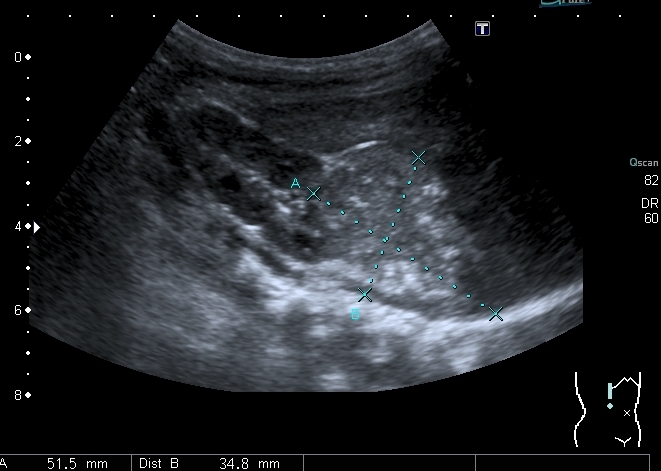

При УЗИ: печень резко увеличена, больше за счёт левой доли

Правая доля

Паренхима печени -гиперэхогенная , неоднородная, практически полностью замещена нодулярными образованиями, некоторые из них с "гало" и кальцификацией